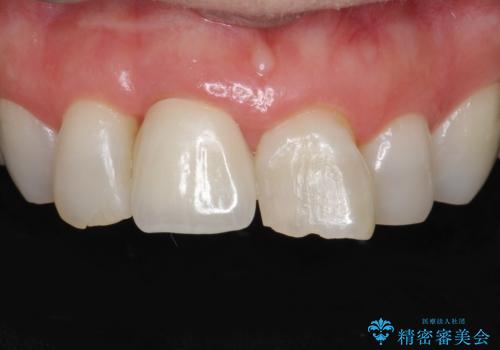

ぶつけて埋まってしまった歯は、場合によって矯正治療で引っ張り出すことで保存することができます。

今回は歯の神経が死んでしまっていたため、根管治療後に被せ物を装着して見た目の綺麗さを回復しました。